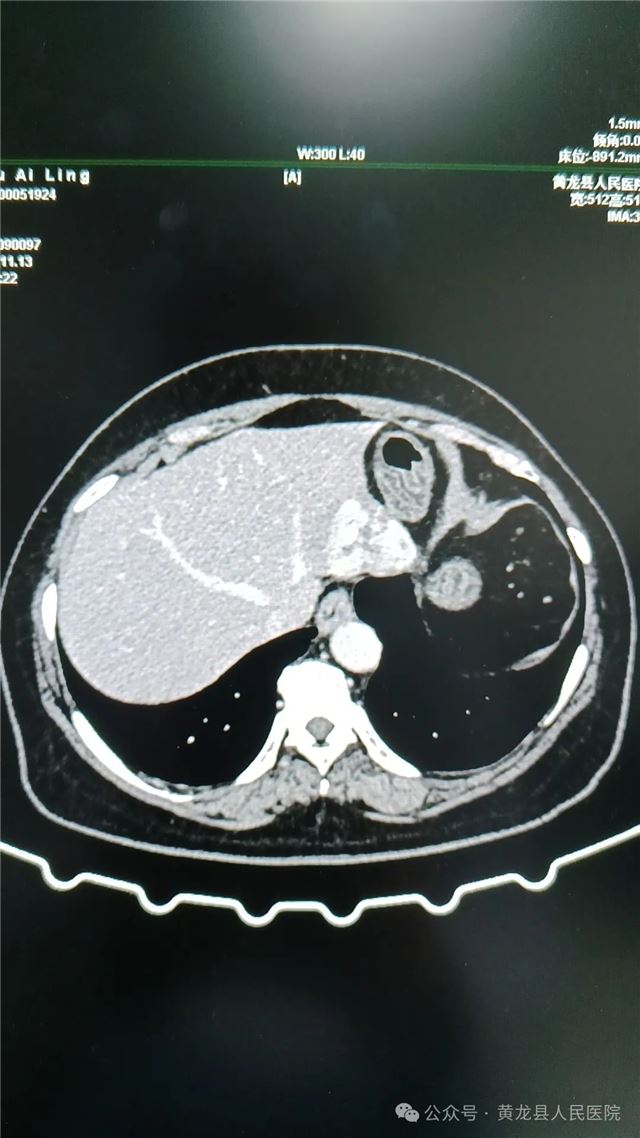

1,术前上腹部CT(平扫、增强)

患者女,58岁,在体检时发现肝占位性病变,经进一步检查后确诊“肝血管瘤”。

临床党小组组长、外科主任方继荣,唐都医院专家贺小军组织外科医务人员为患者进行全面细致评估,开展多次讨论制定出具体周密手术方案,将治疗方案详细告知患者及家属征得同意后,在手麻科协助下,外科专家团队顺利为患者实施“腹腔镜下肝血管瘤及部分周围肝组织切除术”,手术顺利,术中出血少。病理结果回报:(肝)海绵状血管瘤。术后患者恢复快,无明显疼痛,短时间内即可下床活动并进食。目前,该患者已康复出院,对手术效果非常满意,并对外科医务人员表示感谢。